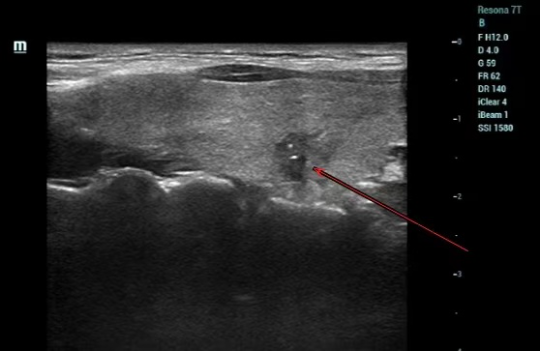

2023年,慕慕来到了深圳市三医院进行体检,在进行B超检查的时候,医生在她的甲状腺处发现了一个7毫米的结节。虽然结节比较小,但是综合形态、边界、血流以及有无钙化灶等情况,体检医生将其分类为4a(即结节有一定恶性风险,需进一步检查)。